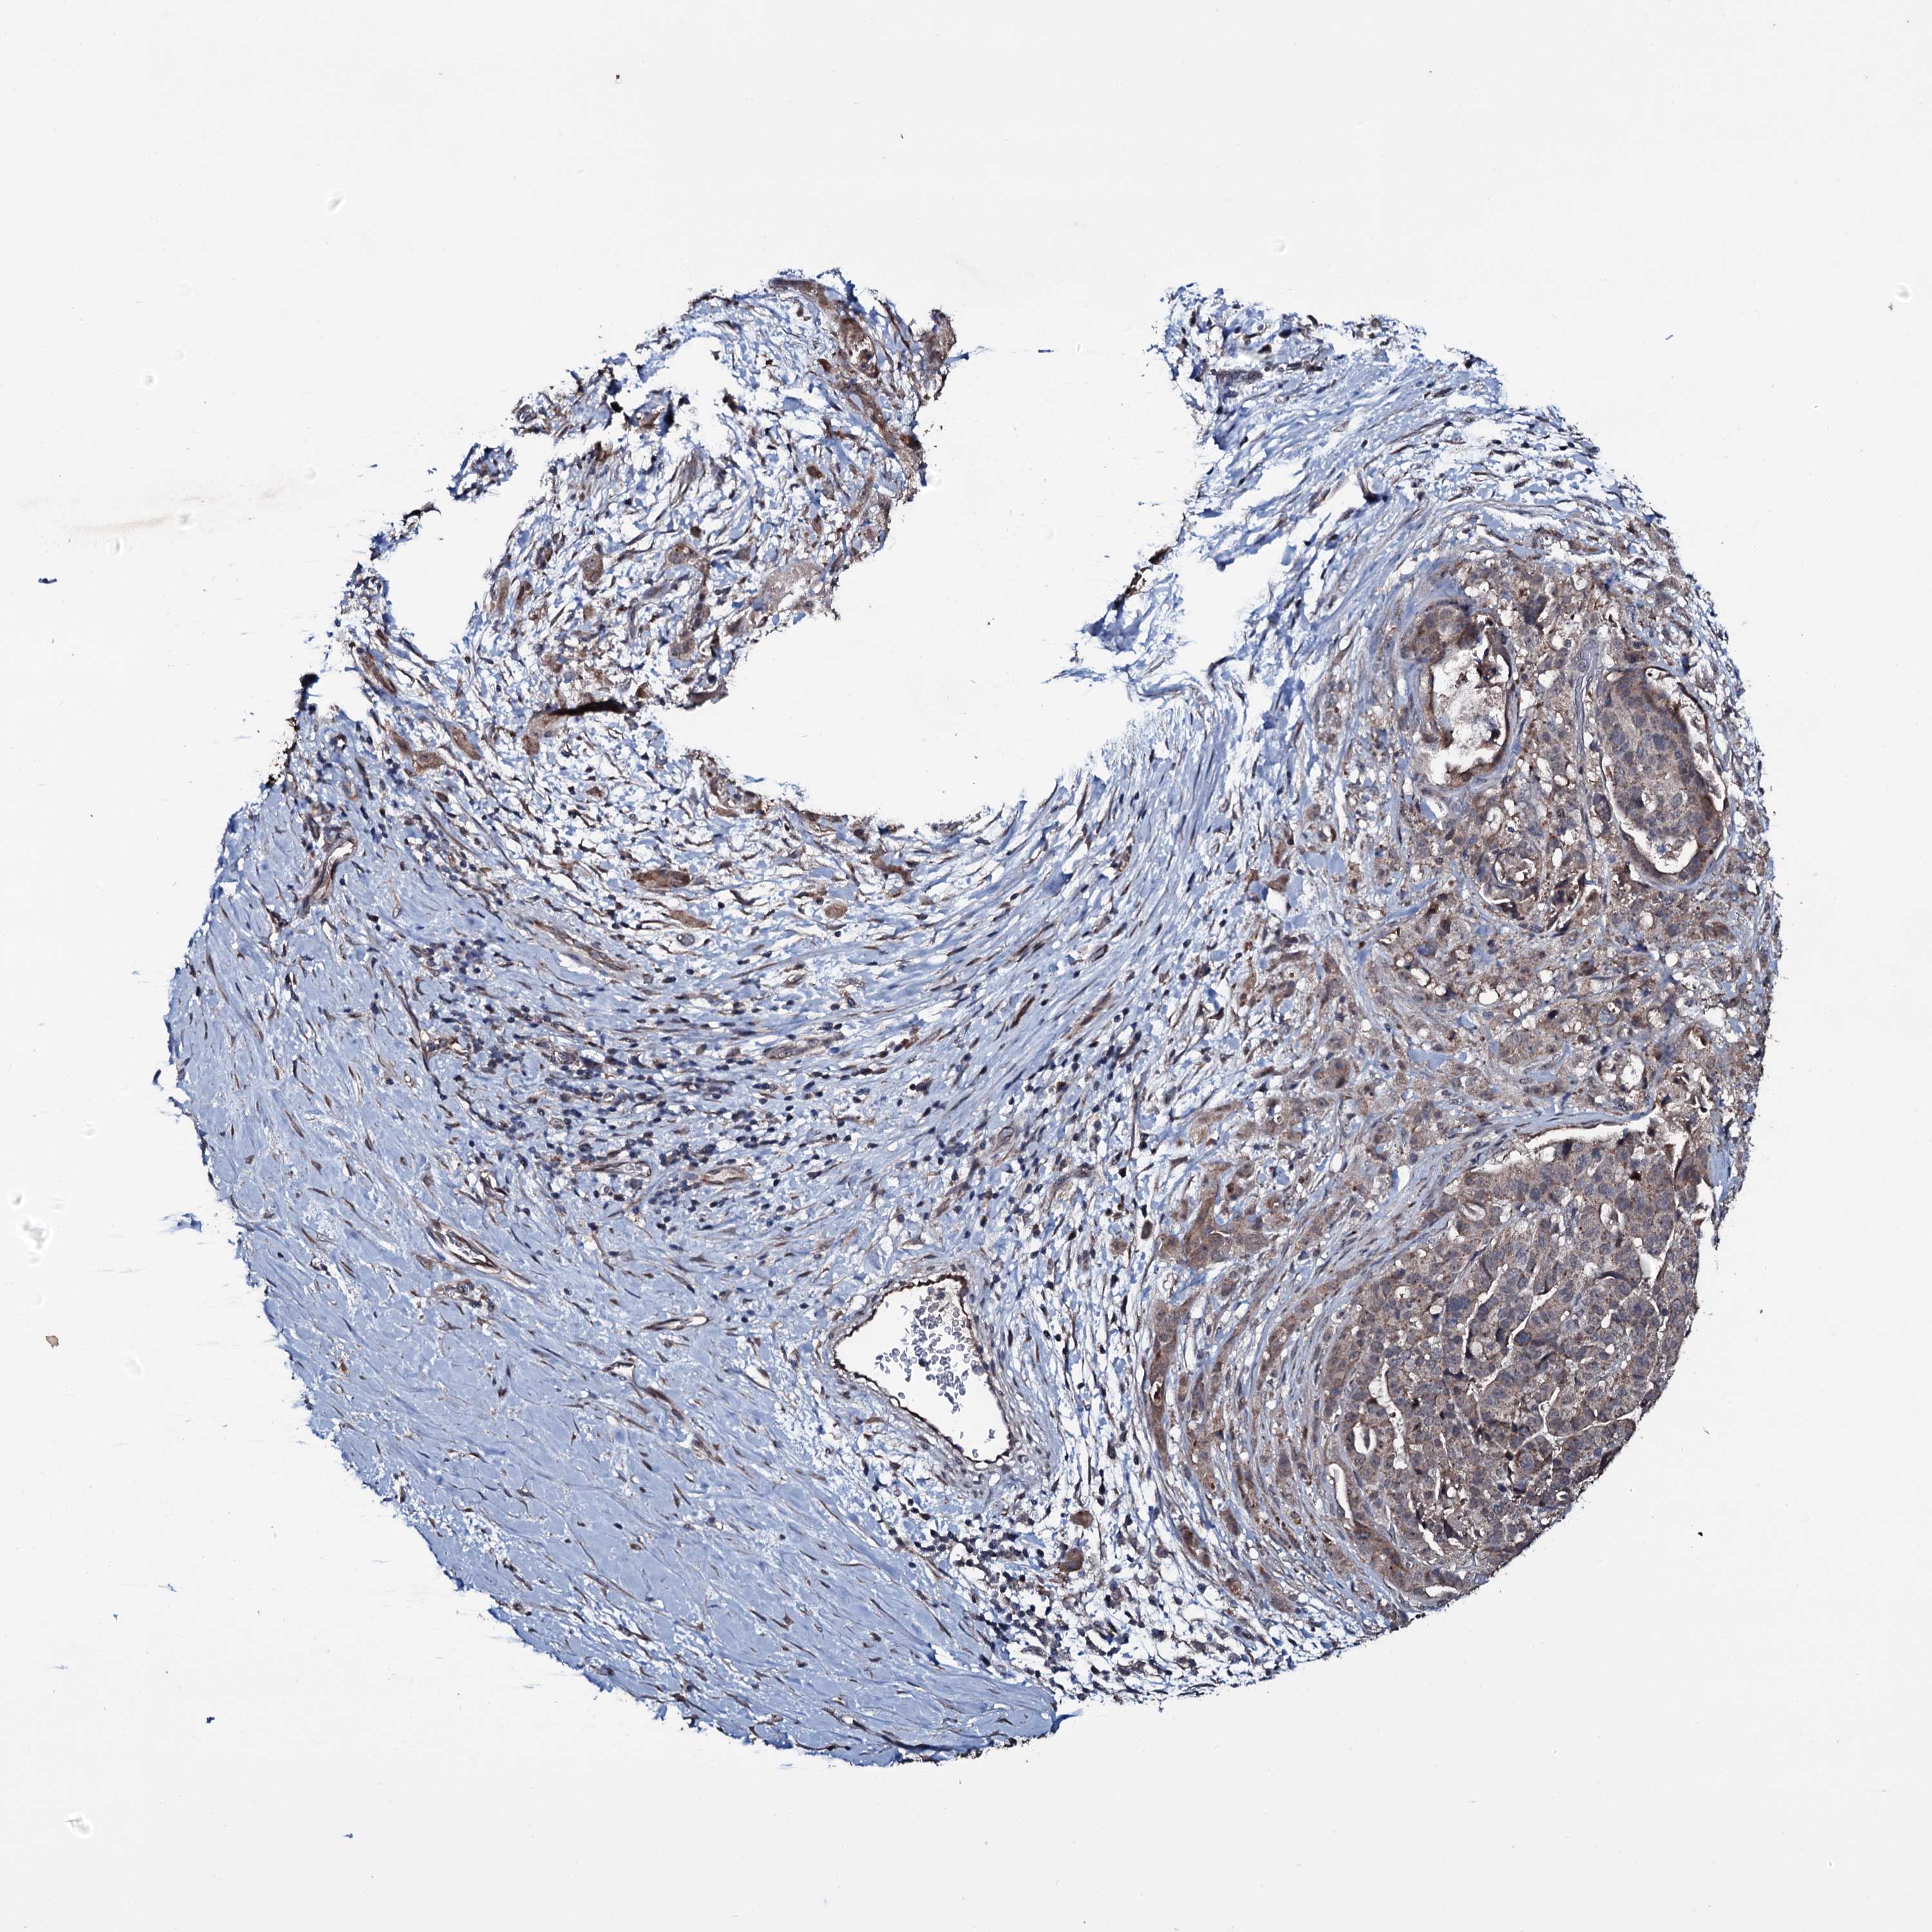

STOMACH CANCER - Protein expressioni

A mouse-over function shows sample information and annotation data. Click on an image to view it in a full screen mode. Samples can be filtered based on level of antibody staining by selecting one or several of the following categories: high, medium, low and not detected. The assay and annotation is described here.

Note that samples used for immunohistochemistry by the Human Protein Atlas do not correspond to samples in the TCGA dataset.

Antibody stainingi

Antibody staining in the annotated cell types in the current human tissue is reported as not detected, low, medium, or high, based on conventional immunohistochemistry profiling in selected tissues. This score is based on the combination of the staining intensity and fraction of stained cells.

Each image is clickable and will lead to virtual microscopy that enables deeper exploration of all samples and also displays staining intensity scores, fraction scores and subcellular localization as well as patient and tissue information for each sample.

Antibody HPA039083

Antibody HPA046344

Staining

High

Medium

Low

Not detected

Intensity

Strong

Moderate

Weak

Negative

Quantity

>75%

75%-25%

<25%

None

Location

Nuclear

Cytoplasmic/membranous

Cytoplasmic/membranous,nuclear

Adenocarcinoma, NOS

Adenocarcinoma, High grade